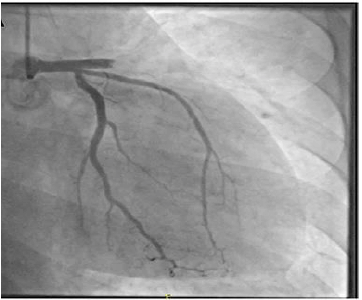

A coronariografia acima é compatível com a seguinte emergência cardiovascular: